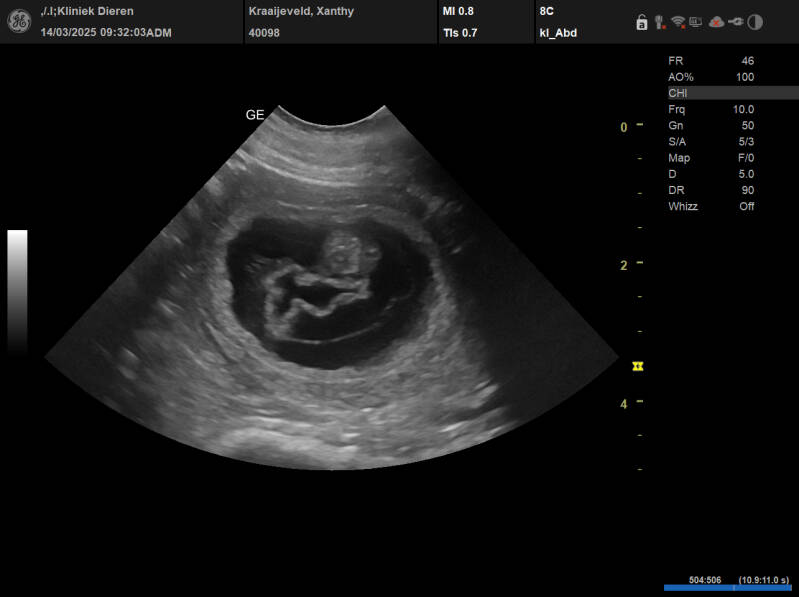

Vandaag is het een spannende dag. Hoewel ik denk dat Xanthy drachtig is, is het toch altijd spannend of het echt zo is.

Richard ging ook mee voor de echo. Hij had nog nooit zo'n echo gezien. We werden door de dierenarts geroepen en Xanthy mocht op de onderzoekstafel staan. Ze kreeg gel  op haar buik en de dierenarts ging even snel over de buik. Ik zag al meteen dat Xanthy drachtig was en de dierenarts ook.

We hebben daarna rustig gekeken de dierenarts heeft het uitgelegd aan Richard. Hij heeft er toch wel een aantal pupjes gezien.

We zijn zo blij. Er komen weer van die lekkere kleine knuffels.